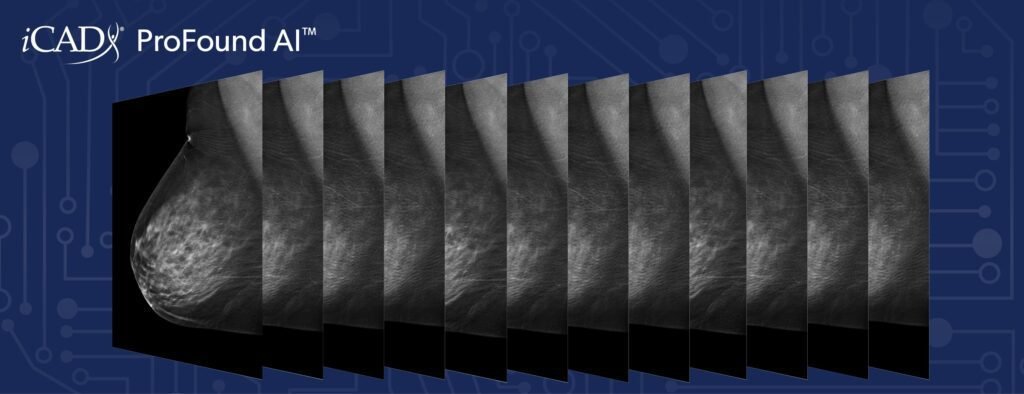

How does ProFound AI work?